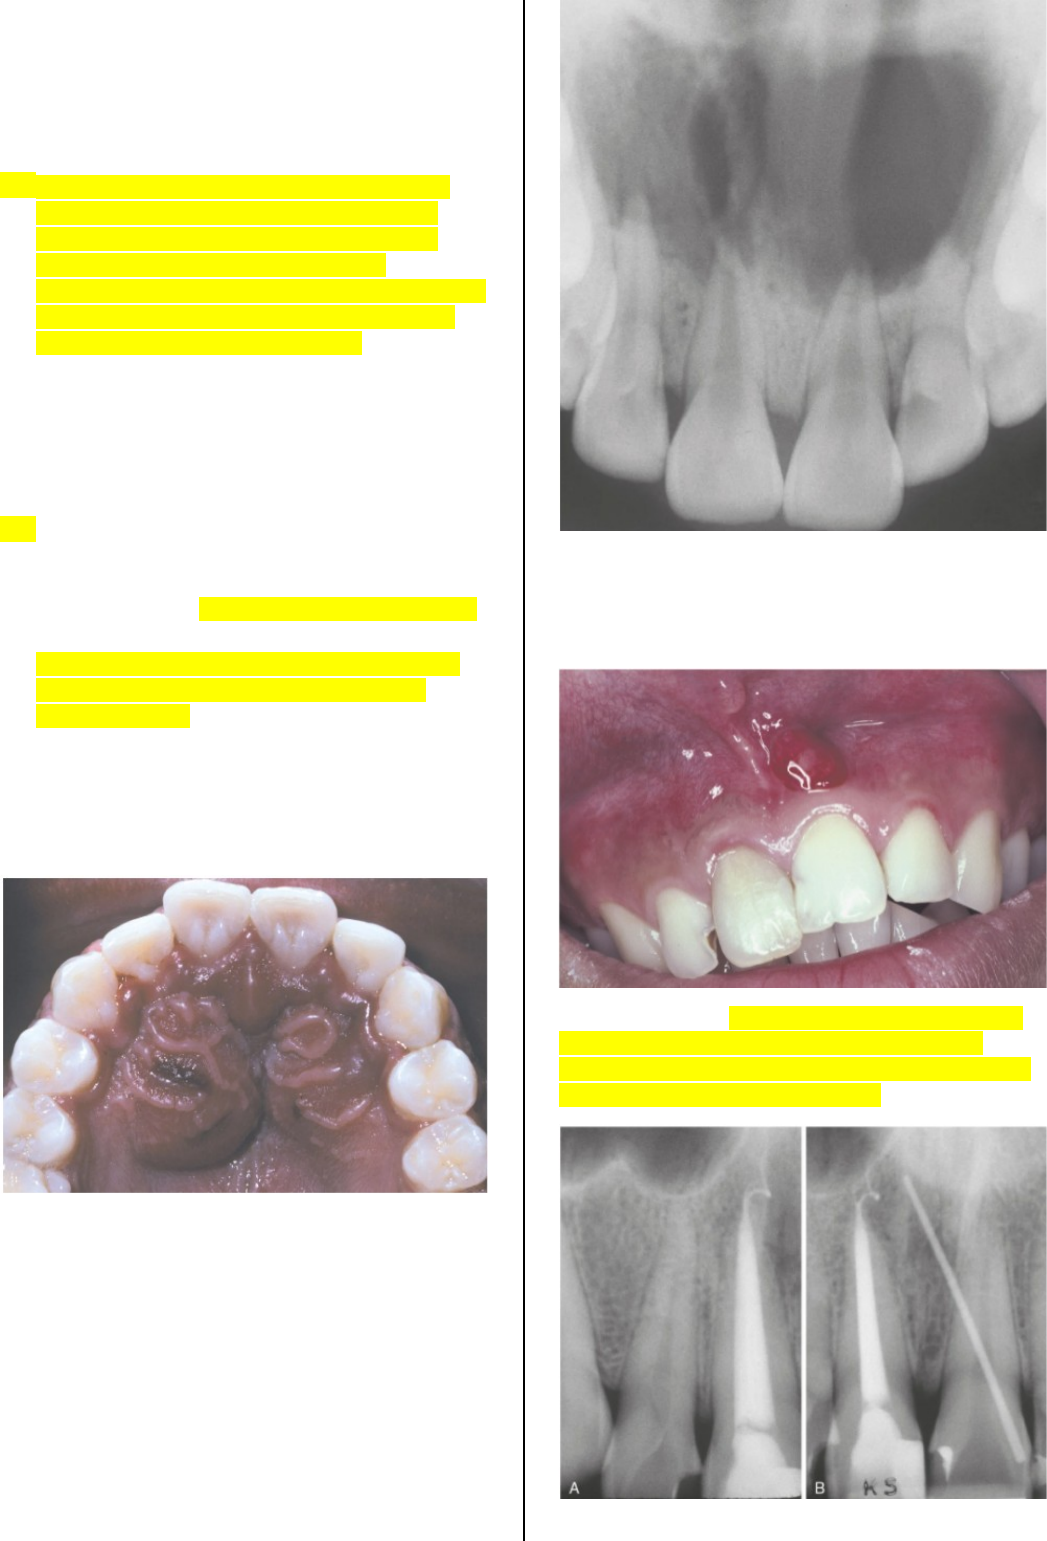

Grátis: AULA 07 Osteomielite (PARTE II) e lesões potencialmente malignas - Material Claro e Objetivo em PDF para Estudo Rápido

image size: 1122x1419

image size: 1440x1080